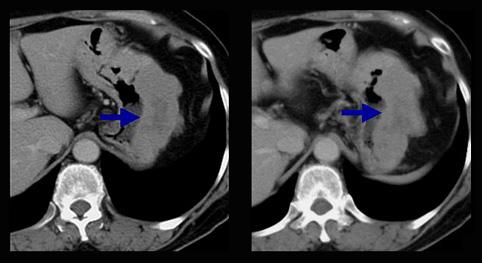

Criteria of Hist.ClassificationMalignant Lymphoma/Malignant lymphoma

LocationStomach/More than one of above

Technique, MethodCT

Size40 -

Depth of Tumor Invasionserosa (adventitia)